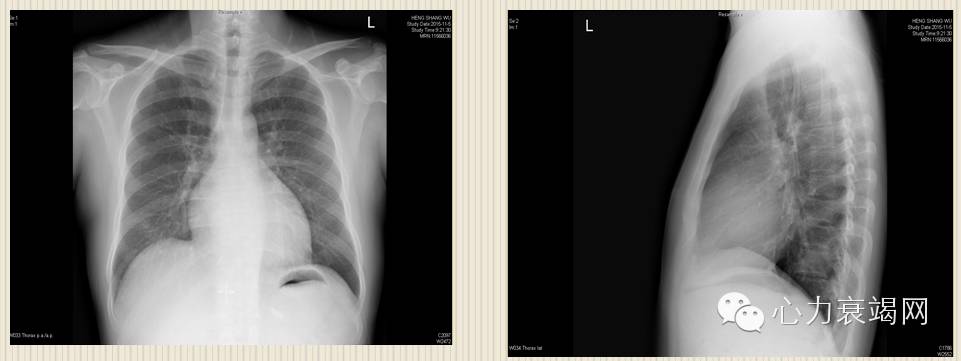

两肺纹理大致正常,未见实变; 主动脉结不宽; 肺动脉段平直; 左室圆隆; 心胸比:0.51

2﹒胸部X线

心脏增大,搏动减弱。